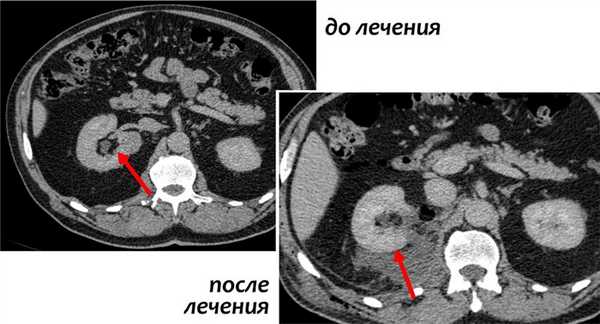

На изображении двустороннее поражение почек и поражение костей у пациента с В-клеточной лимфомой.

Вот еще один пациент с лимфомой, локализированной в средостении, поджелудочной железе (стрелка) и в обеих почках.